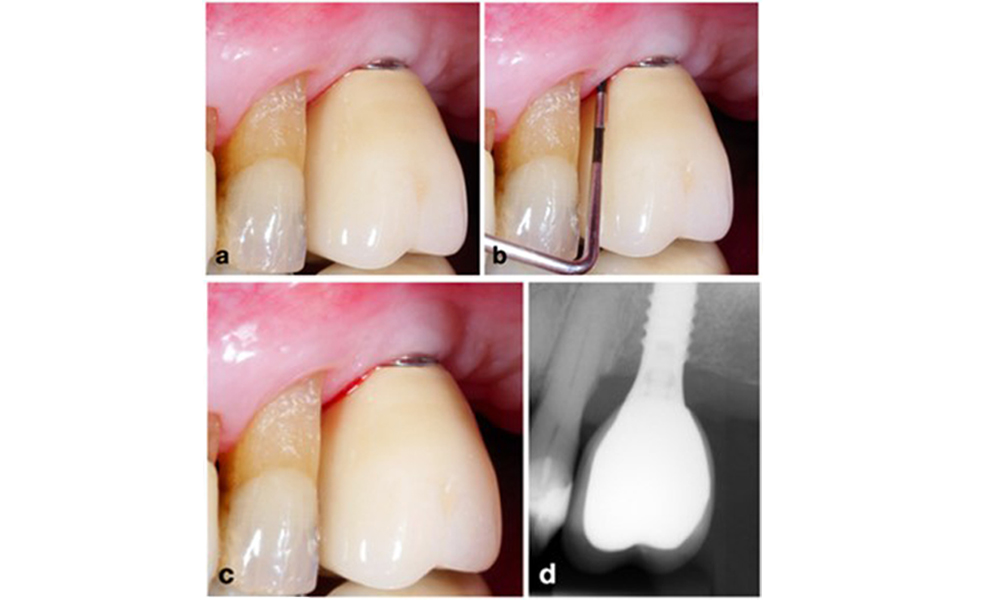

Finally, it has been observed, that implants with less than 2 mm of keratinised mucosa exhibit an increased prevalence of peri-implantitis, and higher plaque accumulation and bleeding indices (Ramanauskaite et al. 2022). This highlights the importance of considering keratinised mucosa augmentation in peri-implantitis prevention and management (figure 14).

An implant lacking keratinised mucosa at the buccal aspect (a). To increase the width of the keratinised mucosa, a gingival graft was placed (b), enhancing oral hygiene effectiveness (c).